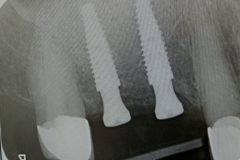

Implants placed using a digitally planned stackable surgical guide following alveolectomy, ensuring ideal positioning and a stable foundation for full-arch restoration.